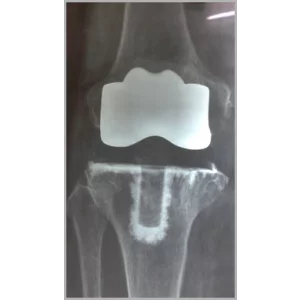

Right Total Hip Replacement And Right Total Knee Replacement In Single Stage Only